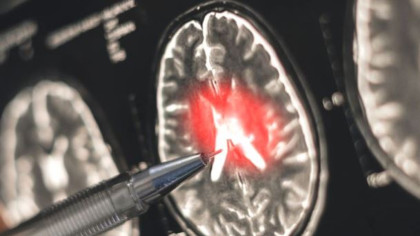

Potrivit crucea-rosie.ro, o concentraţie foarte mare de monoxid de carbon vă pune viaţa în pericol, fiind de ajuns câteva minute de expunere pentru a suferi un atac cerebral, infarct, pierderea memoriei şi, în cele din urmă, deces.